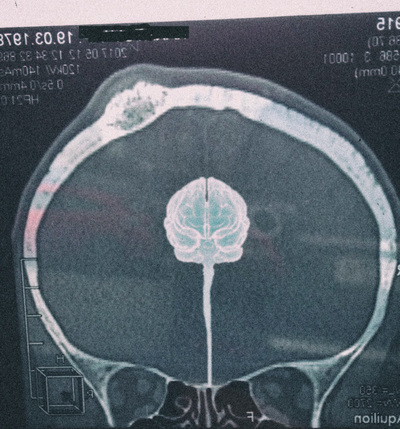

Остеохондрома выглядела так

Она образовалась где-то 8-10 лет назад именно после удара головой об дверной косяк и все это время мне не мешала. У меня не было никаких болей, единственное когда надавить на саму шишку было больнее, если давить с таким же усилием на любую другую точку черепа. Первая причина, по которой я решился на удаление, эстетическая. Потому что лет через 5-7 я облысею, а здоровья потом точно больше не будет, поэтому лучше сейчас. После этого снимка появилась вторая причина. Чисто теоретически можно было бы и дальше с ней жить и постоянно наблюдаться, но я уже был настроен решительно. Диаметр по описанию 2.5 см в горизонте и около 2 см по вертикали.

Операции по удалению опухолей из головы занимают 5-6 часов, рекорд моего доктора 15,5 часов (его слова). Так как внутрь черепа мне не лазили, моя операция заняла 2.5 часа. Опасность была в том, что остеохондрома у меня близко расположена к центру черепа, где проходит вена, в которую сливается вся кровь, прошедшая через мозг. Называется эта вена синус. Я ни разу не медик, поэтому пишу все со слов доктора, который пояснял мне максимально доступным языком. Если пережать синус на 2/3 у человека отнимутся конечности, полностью пережатый синус вызывает смерть. Поэтому во избежание повреждения синуса, остеохондрому обпилили вокруг и обломали череп у синуса. Т.е. представляете, вам надо выпилить круг, но из-за ширины электролобзика не можете полностью это сделать и поэтому выламываете остатки.